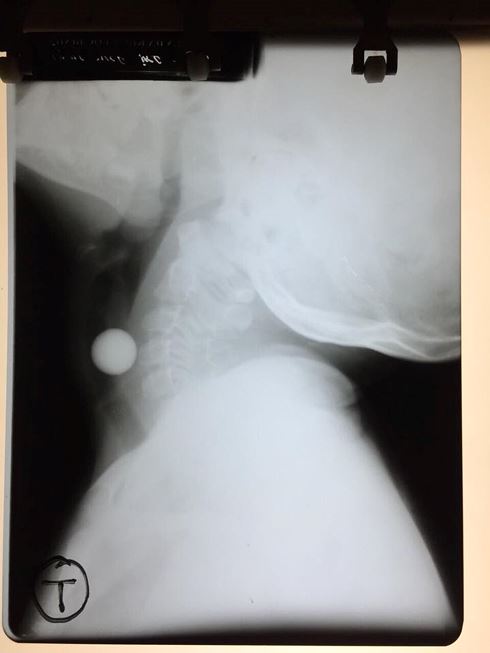

06/06/2018 18:07Cứu sống bé gái 6 tuổi nuốt viên bi vào khí quản

Sáng 6/6, Khoa Tai mũi họng, Bệnh viện Đa khoa tỉnh Lạng Sơn cho biết, vừa tiếp nhận trường hợp bệnh nhân Nông Thị H (SN 2012), trú tại xã Yên Khoái, huyện Lộc Bình, Lạng Sơn nhập viện do nuốt phải dị vật. Trước vào viện khoảng 3 giờ, người nhà phát hiện H nuốt phải viên bi, sau đó bé có biểu hiện buồn nôn, hoảng loạn.

Các bác sĩ đã tiến hành đặt ống nội khí quản, gắp dị vật thành công, lấy ra một viên bi có kích thước 1,5cm. Hiện tại, sức khỏe của cháu bé đã dần ổn định.

Trước đó, Bệnh viện đã tiến hành gắp dị vật thành công cho nhiều trường hợp, trong đó có ca gắp dị vật đường thanh khí quản cho bé trai 2 tuổi.